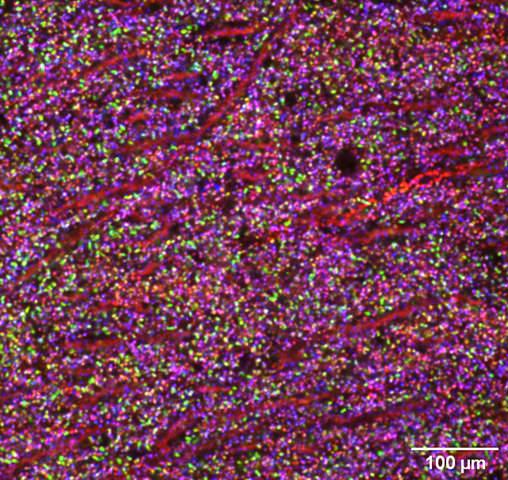

Microscopic image of a mouse brain

Image of mouse brain tissue showing individual synapses as colored puncta. Three different proteins were labelled with green, red and blue dyes. The diversity of synapse types shown by the rainbow of colors results from the combined expression of these three proteins.